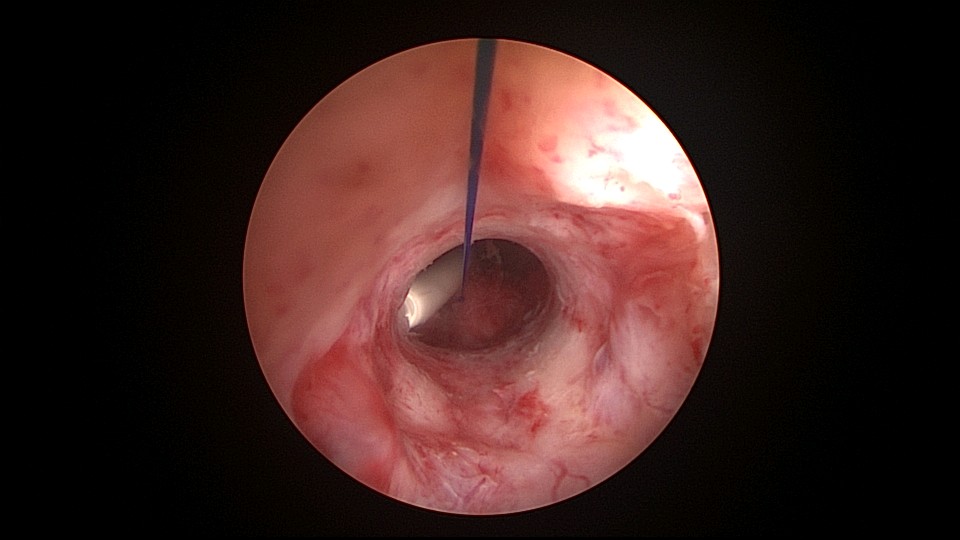

患者42,G3P1,顺产1次。子宫腺肌症伴腺肌瘤,逐渐加重的痛经,2024年11月起皮下注射亮丙瑞林3个周期,出现潮热出汗症状。2025年4月,要求放置曼月乐环并固定,子宫后位,宫深9cm,宫腔上段右侧粘连,宫腔下段宽大。4-0不可吸收线将曼月乐缝合固定于宫腔上段后壁,缝线上靠近曼月乐间距1cm左右打3个结,缝合1针,将1个线结拉过缝合处肌层,利用子宫肌层线结卡压固定曼月乐,避免打结推结。术后多次复查B超,曼月乐位置正常,环顶端距宫底1.6cm。